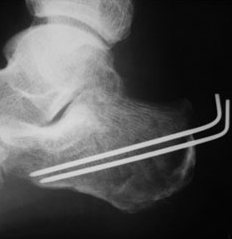

4. 중골 골절

높은 곳에서 뛰어내리거나 해서 발뒤꿈치를 바닥에 강하게 접촉했을 때 주로 나타 납니다. 이것은 졸골 위에 있는 거골과의 관절면에 편차를 발생시킬 수 있는데, 이 어긋나는 부분에 체중이 실리게 되면 매우 강한 통증이 올 수 있습니다.

중골 골절의 치료는 다른 발골절의 치료보다 어렵다고 알려져 있으며, 부상 당시의 상황에 따라 골절의 형태가 복잡해지고, 후유 장애로 남아 오랫동안 발 통증이 지속될 수 있습니다.